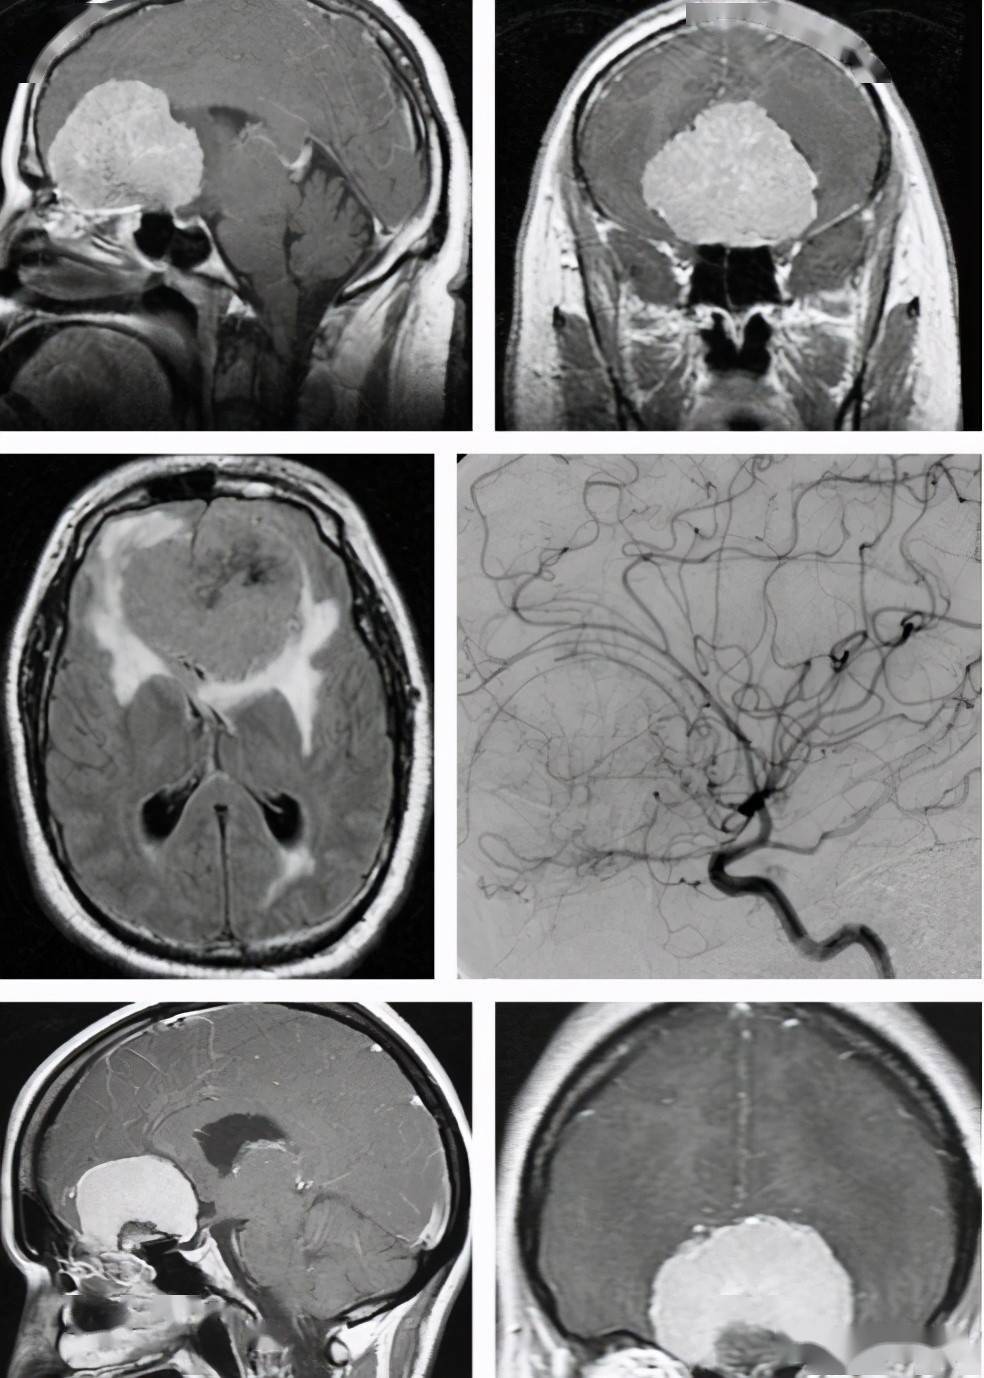

经双侧额下入路显微手术切除巨大嗅沟脑膜瘤1例

一例嗅沟巨大脑膜瘤全切手术分享

嗅沟巨大脑膜瘤

嗅沟脑膜瘤(olfactory meningioma)mri-ct病例影像诊断分析